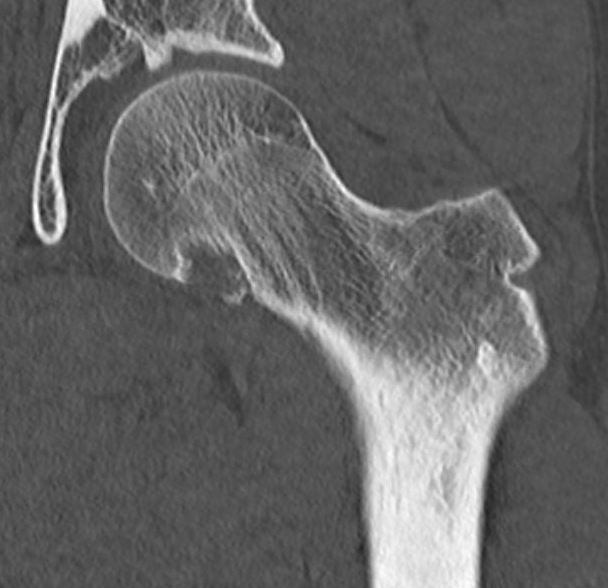

Histology

Biopsy periosteal chondroma

DDx Chondrosarcoma

Bland hyaline cartilage